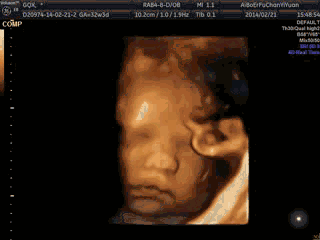

比如说突然加大的噪音 , 或者妈妈走路时候的晃动 , B超时检查的探头 , 以及包括光线的照射 , 这些都会对刺激到宝宝作出胎动反应 。 也有专家说到了孕晚期宝宝还会做梦 , 比如说下图 , 你能猜出宝宝做什么梦吗?